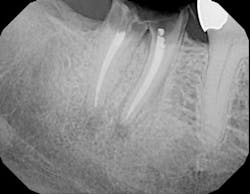

Fig. 1c — Bitewing taken by hygienist three weeks after returning from an outside office reveals nonseated implant abutments on teeth Nos. 18 and 19. Patient complained of too many radiographs being taken.

Fig. 1d — Radiograph taken by a hygienist in a specialty practice. Tooth No. 14 crown was inserted two weeks prior to visit without detection of recurrent decay on tooth No. 15.So what is that risk of radiation?According to the ADA1, the estimated exposure (in millisievert, mSv) is .038 for bitewing radiographs and .150 for a full-mouth series. The average radiation from a cone beam CT scan is .1 to .13 mSv. To give you a comparison, the added dose from cosmic rays during a coast-to-coast round trip flight in a commercial airplane is about 0.03 mSv, whereas radiation from outer space in Denver, Colo., per year is .510 mSv. The average radiation in the United States from natural sources is 3.0 mSv per year. This is not to say that dental radiographs pose no threat. We certainly want to minimize exposure, especially in our high-risk patients such as preganant women, breast-feeding women, and children.How often should we take dental X-rays?This answer, of course, depends on the individual patient, specifically age and disease risk. According to the ADA2, an adult (over 18) with a high caries/periodontal disease progression risk would need radiographs every six to 18 months. On the other hand, an adult with low risk would require X-rays every two to three years. Similarly, a child (under 18) with a high caries risk would need X-rays every six to 12 months vs. a low-risk child every one to two years. In summation, as hygienists, we not only have to be nonsurgical periodontal therapists, but we also have to be educators. We need to take that extra time and recite these timetables and exposure risks to our patients so they can have a better understanding of the importance of the dental radiograph. We also have to make sure that if the patient has traveled to another office to receive care, we don’t rely on other practitioners or assistants to have correctly identified possible pathology. The buck has to stop with us. Author bioRebekah A. Duffy, RDH, has been a hygienist in private practice for more than 10 years. She has lectured and written articles involving peri-implant maintenance and soft-tissue considerations. She currently works in a periodontal practice in New York City, N.Y.References1. Adapted from Frederiksen NL. X-Rays: What is the Risk? Texas Dental Journal. 1995; 112(2):68-72.2. American Dental Association, U.S. Food & Drug Administration. The Selection of Patients For Dental Radiograph Examinations. Available on www.ada.org.